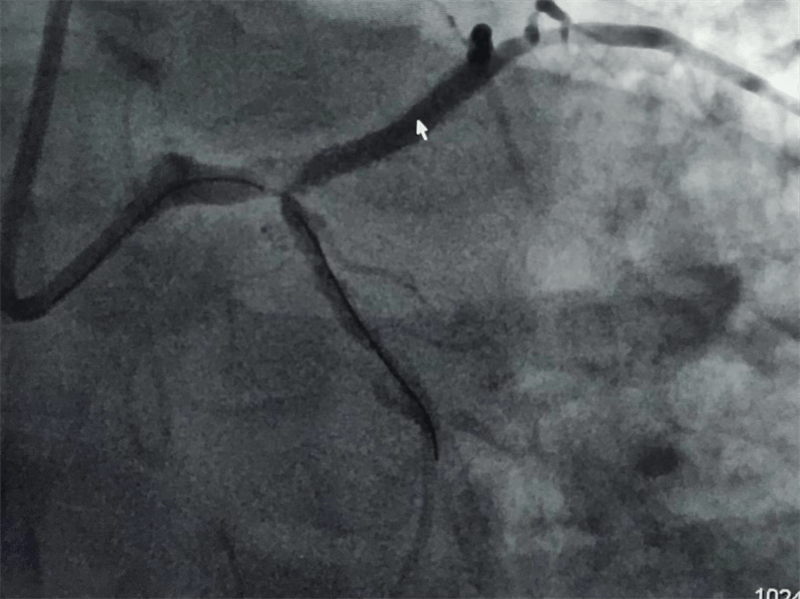

挽救患者生命,挽救一个家庭的希望!当导丝通过病变区域时,大家的心都紧张了起来,经过精细、快速的操作,手术顺利完成,原来像头发丝一样粗细的“血路”,终于恢复了正常!

我们结合患者病变特点,对回旋支支架内闭塞病变处药物球囊治疗,左主干病变植入1枚支架,术后,造影显示左主干病变处支架植入状态良好,血管内超声显示支架贴壁良好,患者血压、心率稳定,症状完全缓解,并安全返回重症监护室进一步治疗,术后张大伯无明显不适,生命体征稳定,病情明显好转。